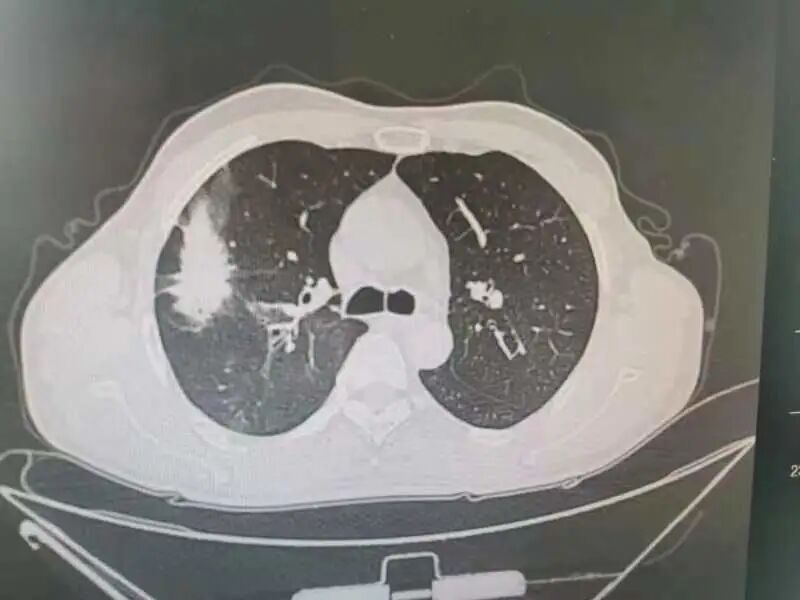

60岁的刘先生平时身体一直不错,登山、跳绳、骑行样样行。像他这样的年龄血压、血糖等都在正常值范围内,身体素质甚至比年轻的小伙子还好。因为没有这疼那痒,五年内从没体检过。 上个月不小心被车撞了一下,到辽宁省肿瘤医院拍了个肺部CT进行检查,这一查不要紧,除了受损的两根肋骨外,“眼尖”的医生居然在CT片子上发现了一个“恶魔”,在其右肺上叶有一个接近5cm的肺结节。 影像资料 辽宁省肿瘤医院胸外科团队接诊后,耐心地询问刘先生,可刘先生既没有吸烟史也没有癌症家庭史,每天在公园暴走上万步的刘先生,会跟“肺癌”这两个字联系在一起吗? 影像资料 为了不给刘先生及其家属带来恐慌,又不能耽误病情,胸外科团队请来了专家为其进行多学科会诊(MDT),“我们不敢冒然行事,也不敢错过手术最佳时机,因为从这个肺结节的形态上来看,如果是肺癌的话,行手术根治术+淋巴清扫,预后效果应该还是不错的”。 手术中 经多学科会诊,专家们建议为刘先生行CT引导下穿刺,以进一步明确病理。病理结果出来后,跟专家们的预想差不多,病理提示“肺腺癌”,胸外科为刘先生做了单孔胸腔镜下的肺癌根治术+淋巴清扫术。术后刘先生恢复很快,5天就出院了。因为是早期肺癌,发现得早,及时手术切,刘先生并不需要化疗、放疗,刘先生悬着的心终于放下了,说道“要不是这场车祸,不然还不知道什么时候会发现,也有可能发现时就是晚期了呢” 早期肺癌治愈率高,定期体检是关键。祸兮福之所倚,福兮祸之所伏。短短一个月内,刘先生经历了“车祸——肺结节——肺癌——手术根治”的跌宕人生。像刘先生这样因为外伤检查住院而意外发现早期肺癌的患者,医院也收治了不少。因为早期肺癌相当隐匿,几乎没有什么症状。如果缺乏定期体检,不做胸部CT,早期肺癌是难以发现的。而等患者发现时就已经到了中晚期了,不仅治疗复杂费钱,效果还不好。 辽宁省肿瘤医院胸外科专家介绍,早期肺癌治愈率较高,其中原位癌及微浸润腺癌治愈率可达90%--100%,且不需要放疗、化疗,治疗费用低,生存质量也高。而中晚期肺癌的五年生存率只有20%--50%。所以,定期体检非常重要。但值得注意的是,大部分肺结节是良性的,只有30%--40%的肺结节可能是早期肺癌。即便是早期肺癌,通过微创手术切除治疗效果也较好。 关注!关注!关注! 辽宁省肿瘤医院疫情期间 门诊就诊攻略 辽宁省肿瘤医院互联网医院 “在线复诊”上线了 稿件、图片来源:胸外科一病区 编辑:刘换 洪流 责编:郑阳 你“在看”我吗?